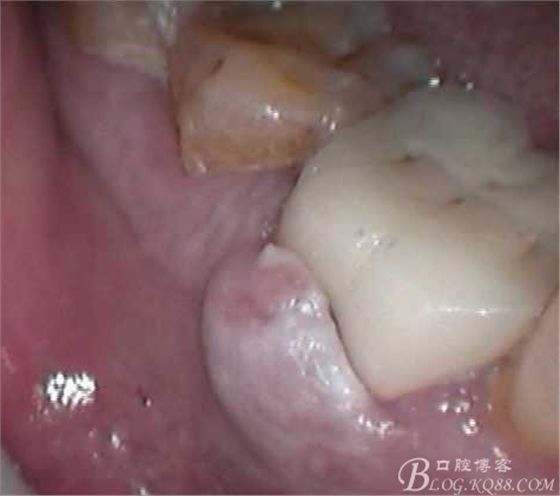

頰側(cè)牙齦腫脹